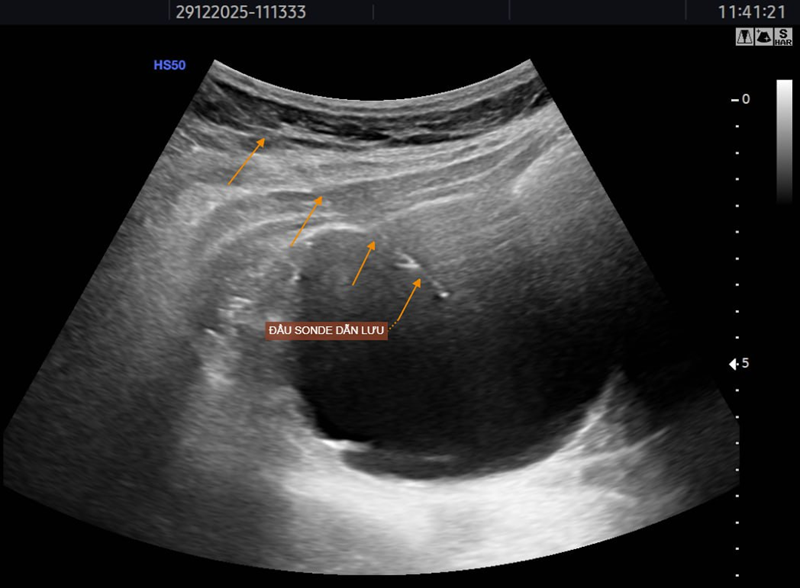

Hình ảnh hút dịch nang thận bằng sonde dẫn lưu dưới hướng dẫn siêu âm

Lượng dịch hút ra từ nang thận lên tới 120ml

BSCKI. Trần Văn Thụ – Phó Giám đốc Trung tâm Chẩn đoán hình ảnh MEDLATEC là người trực tiếp thực hiện kỹ thuật tiêm cồn nang thận cho bệnh nhân. Kết quả sau điều trị vô cùng khả quan khi thể tích nang giảm tới 78%. Bà N. được hướng dẫn tái khám định kỳ theo dõi bằng siêu âm.